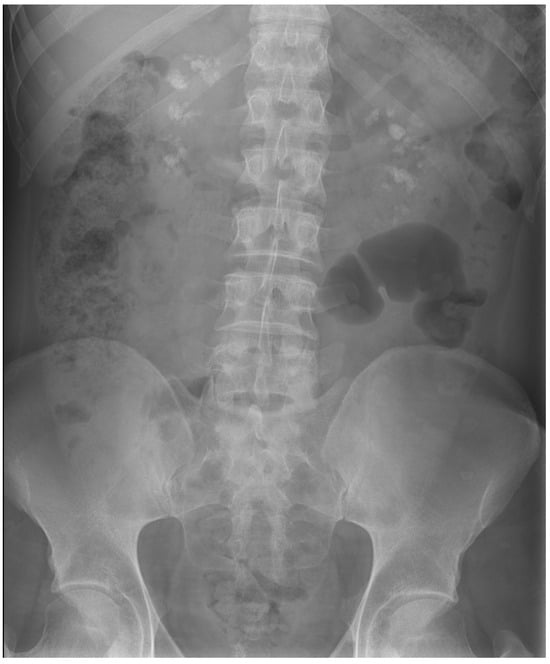

| Last imaging test | CT scan: bilateral lithiasis and microlithiasis, with nephrocalcinosis | US: bilateral microlithiasis | CT scan: atrophic kidneys with a pattern of medullary nephrocalcinosis | CT scan: microlithiasis | US: no lithiasis | CT scan: microlithiasis |